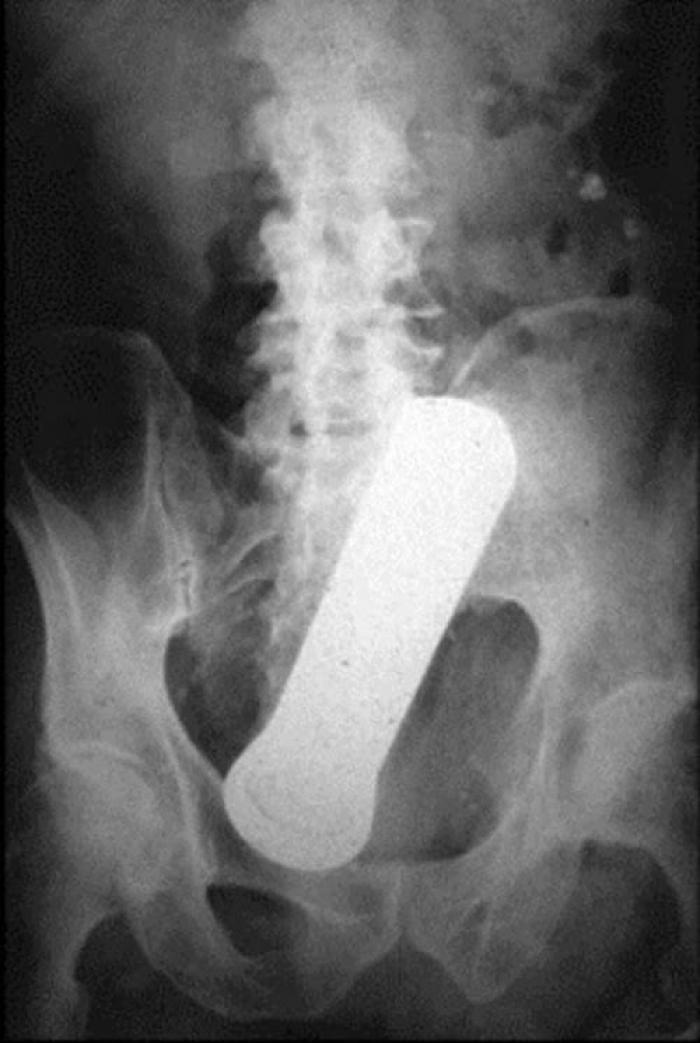

Razele X ne dovedesc că oamenii "pierd" adesea o mulțime de lucruri în propriul corp.